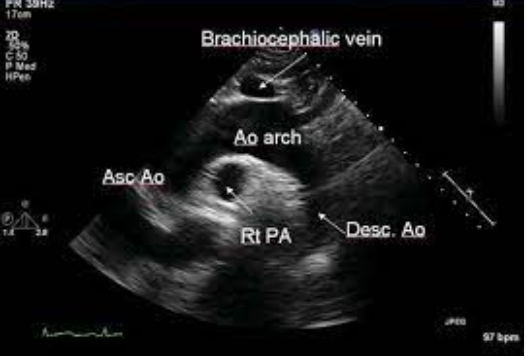

normal anatomy

A